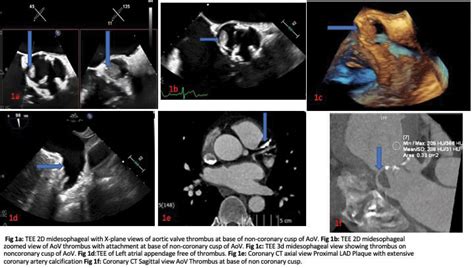

A Transesophageal Echocardiogram, or TEE, is a specialized ultrasound of the heart. Unlike a standard echocardiogram, where the probe is placed on the chest wall, a TEE involves passing a thin, flexible probe down the esophagus. Because the esophagus sits directly behind the heart, this imaging technique provides exceptionally clear, high-resolution views of the heart’s chambers and valves, particularly the left atrium.

The primary goal of performing a Tee And Cardioversion together is to rule out the presence of a thrombus (blood clot). If the TEE reveals no clot, the medical team can proceed with the electrical cardioversion immediately, knowing the risk of stroke from a dislodged clot is extremely low. If a clot is discovered, cardioversion is postponed, and the patient is placed on anticoagulation therapy until the clot dissolves.